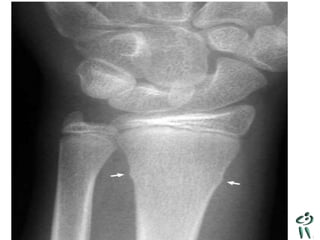

Diagnostic ?

A. Salter 1

B. Entorse cheville

C. Entorse haute

D. Salter 3

E. Avulsion

Fracture de Tillaux

• Salter 3

• Fracture de la portion latéral de

l’épiphyse du tibia distal

• La portion médiane de la physe du tibia

ayant déjà commencé à se fusionner

Conduite

• Atelle postérieure

• Référé 24 heures

• Aviser résident de garde ortho